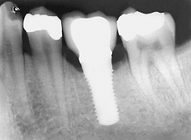

更多单颗后牙缺失 病例 3

36 y M, pain, root fracture 24 with endo RCT before. 5 weeks of soft tissue healing for early implant surgery, with bone graft. 4 months after surgery the tooth was restored. 1.5 y follow up perfect.